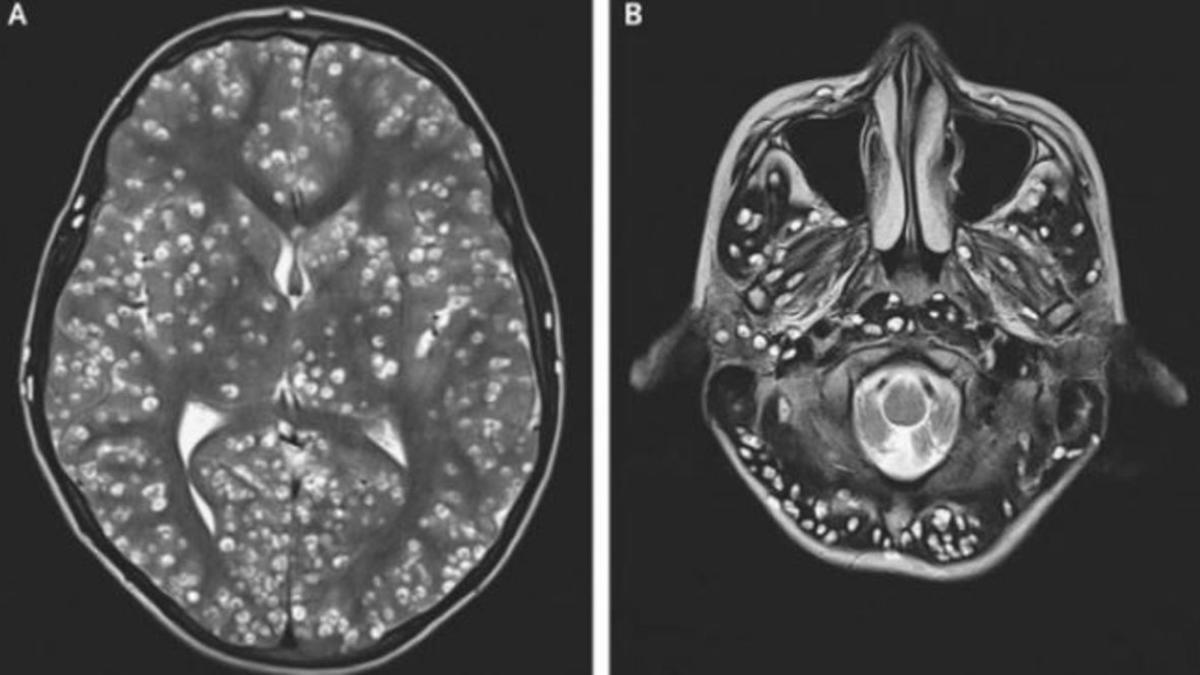

Necesitaron una resonancia magnética para comprobar que tenía lesiones quísticas en la corteza cerebral y el cerebelo, según narran los doctores Nishanth Dev y S. Zafar Abbas, del Colegio Médico y Hospital ESIC, que podrían coincidir con una neurocisticercosis. Es decir, una enfermedad parasitaria del cerebro.